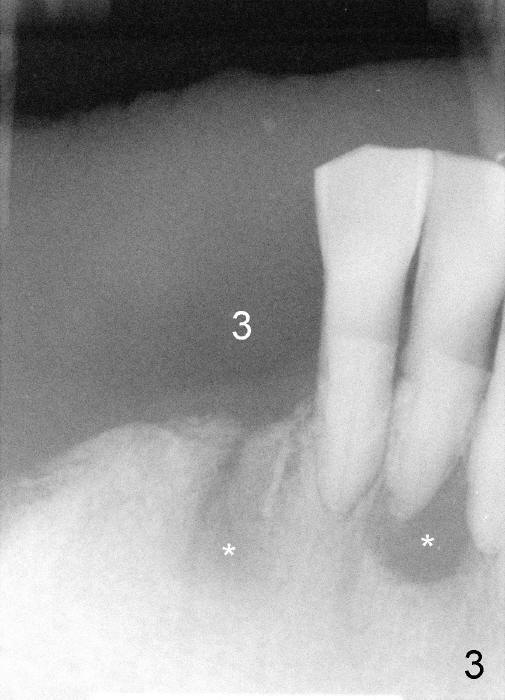

Four months later, he returns and asks for implant restoration.  The ridge at the site of #3 is quite narrow (Fig.5).  While the socket of #3 is radiolucent (Fig.3 * under #3), there is an periapical abscess of the neighboring tooth (separate *).  It appears unsafe to place an implant at the site of #3, although anesthetic has been injected (Fig.5 *).  Instead an implant is placed at the site of #6 (5x14), further away from the infection.